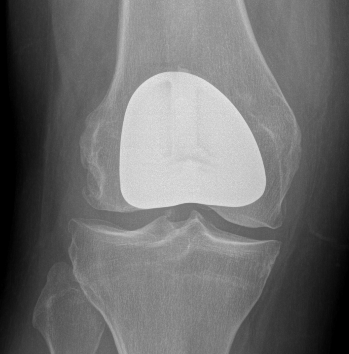

Patellofemoral joint replacement

Technique